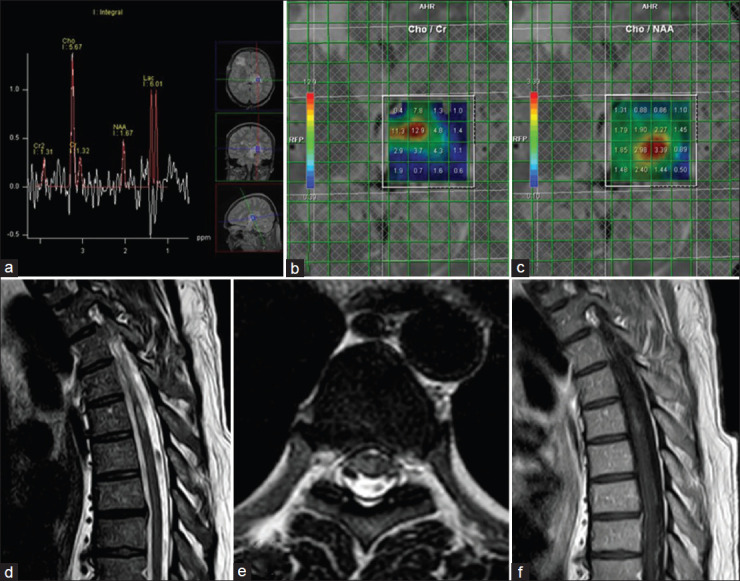

炎性脱髓鞘假瘤(IDP)在临床表现和影像学特征方面与颅内肿瘤相似。具有马尔堡样特征的IDP是一种严重形式的炎症性脱髓鞘性脑脊髓炎,其特点是起病剧烈,病程积极,无缓解,存在肿瘤样中枢神经系统脱髓鞘病变。脑磁共振成像IDP的主要特征包括开放或不完整的环形增强,低T2边缘,外周扩散受限,没有或轻微的肿块效应,以及病灶周围水肿。在脑磁共振波谱(MRS)中,观察到谷氨酸、胆碱和乳酸盐峰升高;然而,脑MRS的发现可能是非特异性和非鉴别的。病理结果显示明显的血管周围淋巴浸润,主要由白细胞共同抗原(LCA)+和PAX5+ B淋巴细胞组成(免疫组化染色),实质和血管周围巨噬细胞(CD68+), Luxol Fast Blue染色可见髓磷脂球,髓磷脂优先丢失,相对轴突保存,轴突球状体形成(肿胀),反应性星形细胞增生(GFAP+和ATRX-)。斑块周围的髓鞘比背景轴突薄。对以往病例报告的回顾显示,对具有马尔堡样特征的IDP进行及时积极的免疫抑制治疗可能会产生良好的反应。以高剂量皮质类固醇开始治疗周期,随后使用环磷酰胺、米托蒽酮、利妥昔单抗或阿仑单抗进行救援性免疫抑制治疗,显示出积极的结果。此外,使用b细胞消耗药物(如rituximab和ocrelizumab)进行维持性免疫抑制治疗,显示出控制疾病活动和改善长期预后的潜力。

Inflammatory demyelinating pseudotumor (IDP) mimics intracranial neoplasms in terms of both clinical presentation and imaging features. IDP with Marburg-like features represents a severe form of inflammatory demyelinating encephalomyelitis, marked by a dramatic onset, aggressive course, absence of remission, and the presence of tumor-like central nervous system demyelinating lesions. Key features of IDP in brain magnetic resonance imaging include open or incomplete ring enhancement, low T2 rim, peripheral diffusion restriction, absent or mild mass effect, and perilesional edema. In brain magnetic resonance spectroscopy (MRS), elevated glutamate, choline, and lactate peaks are observed; however, brain MRS findings can be nonspecific and nondifferentiating. Pathologic findings show prominent perivascular lymphoid infiltrates consisting predominantly of leukocyte common antigen (LCA)+ and PAX5+ B lymphocytes in immunohistochemistry staining, parenchymal and perivascular macrophages (CD68+), some with visible myelin globules on Luxol Fast Blue staining, preferential loss of myelin with relative axonal preservation and the formation of axonal spheroids (swellings), reactive astrocytosis (GFAP+ and ATRX-), and remyelination with thinner myelin sheaths than background axons at the periphery of the plaque. A review of previous case reports revealed that prompt aggressive immunosuppression therapy in the IDP with Marburg-like features may lead to a favorable response. Initiating treatment with a cycle of high-dose corticosteroids followed by rescue immunosuppressive therapy using cyclophosphamide, mitoxantrone, rituximab, or alemtuzumab demonstrated positive outcomes. In addition, maintenance immunosuppressive therapy with B-cell-depleting agents, such as rituximab and ocrelizumab, showed potential for controlling disease activity and improving long-term prognosis.